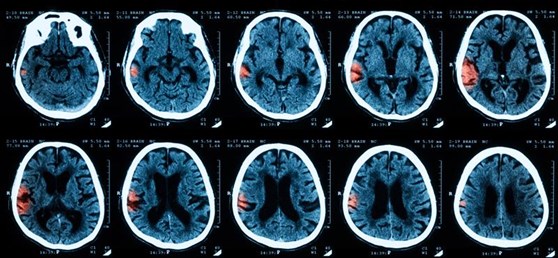

Brain scanning modalities, such as magnetic resonance imaging (MRI) and positron-emission tomography (PET), are invaluable tools for diagnostics and translational research on brain function and disease [4]. However, the inherent complexity and subtlety of a single brain scan can make it challenging for clinicians to accurately assess neurological conditions [5]. AI learning models are starting to study libraries of previous diagnostic cases and analyze huge amounts of data in extremely fine detail. These models can then recognize patterns in the images and better identify lesions or abnormal activity, which can help confirm diagnoses and predict the best treatment avenues on a patient-to-patient basis. Deep neural networks have been implemented to speed up acquisition of MRI data, enhance signal-to-noise ratio (SNR) and resolution, reconstruct and register brain images, and even optimize radiation dosage for advanced processes like theranostic CT scanning [6, 7, 8].

AI-based brain imaging software in development. Machine learning analysis of CT-scans predicts a lesion from patient data very quickly, with high accuracy.